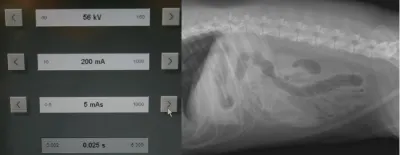

Remember to develop the films with fresh, clean developing solutions-old or exhausted developer will not work for developing technique charts. Examine the films for the setting that gives the best diagnostic quality. In Figure A, the kVp was 56, mA setting was 200, and time was 0.0125 seconds (mAs = 2.5). In this example, the bones are not easily visualized and the film overall is too white (underexposed).

In Figure B, the kVp and mA were left the same and the time was changed to 0.025 seconds (mAs = 5). In this image, the body wall, abdominal organs, and bones can all be readily visualized; this is a proper exposure. In Figure C, the kVp and mA were left the same and the time was changed to 0.05 seconds (mAs = 10). With this higher exposure technique, the ventral body wall cannot be visualized, and the abdomen is too dark (overexposed).